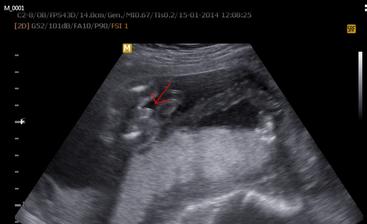

20tt+3 (2014/01/15) .... velký UTZ, vše vypadá Ok a čekáme chlapečka